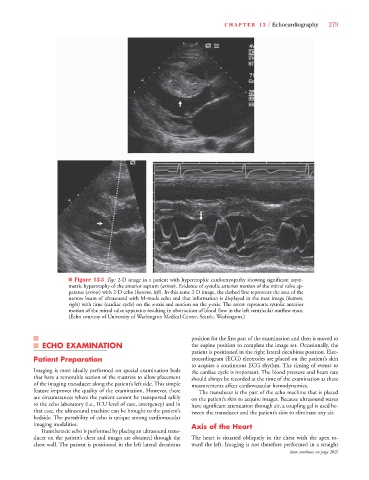

■ Figure 13-3 Top: 2-D image in a patient with hypertrophic cardiomyopathy showing significant asym-

metric hypertrophy of the anterior septum (arrow). Evidence of systolic anterior motion of the mitral valve ap-

paratus (arrow) with 2-D echo (bottom, left). In this same 2-D image, the dashed line represents the area of the

narrow beam of ultrasound with M-mode echo and that information is displayed in the next image (bottom,

right) with time (cardiac cycle) on the x-axis and motion on the y-axis. The arrow represents systolic anterior

motion of the mitral valve apparatus resulting in obstruction of blood flow in the left ventricular outflow tract.

(Echo courtesy of University of Washington Medical Center, Seattle, Washington.)